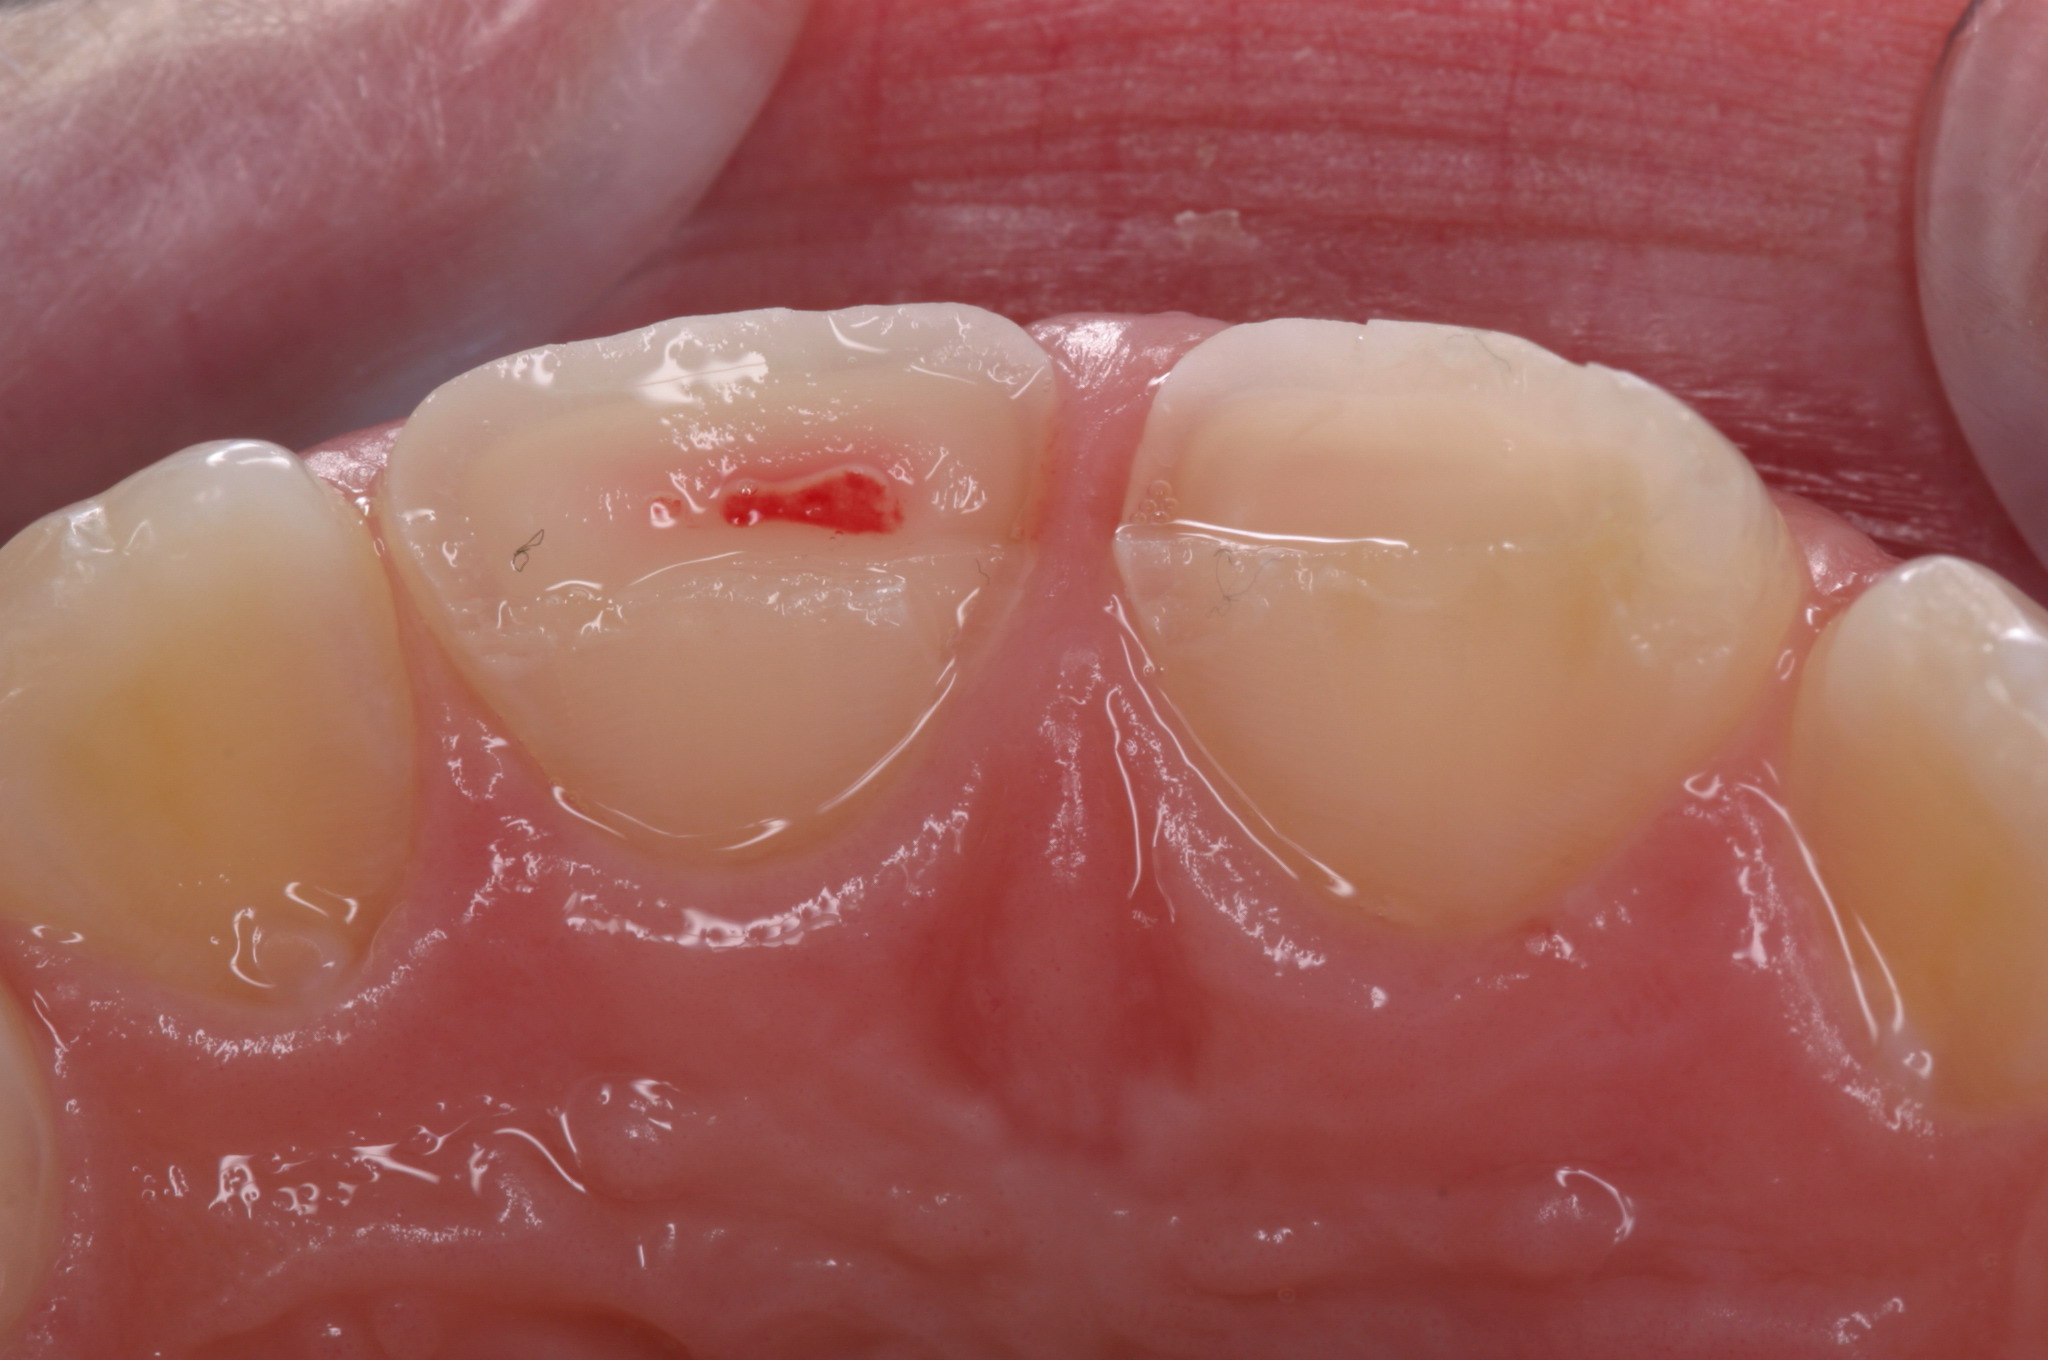

© Dr. Sofia Rehling

Ein Zahntrauma kann zum einschneidenden Erlebnis für den Betroffenen, oftmals ein Kind, werden. Während für den Patienten zunächst die Beseitigung der unmittelbaren Unfallfolgen im Vordergrund steht, muss der Behandler die oftmals weitreichenden Konsequenzen einzelner Therapieoptionen berücksichtigen. Generell geht es darum, alle 5 Gewebe (Zahnhartsubstanz, Endodont, Parodont, angrenzender Alveolarknochen und orale Weichgewebe), die bei einem Zahnunfall betroffen sein können zu berücksichtigen und für sich adäquat zu behandeln.

Bei der Therapie von Zahnfrakturen stehen aus endodontischer Sicht vitalerhaltende Maßnahmen im Vordergrund. Zähne mit nicht abgeschlossenem Wurzelwachstum können so ihr Wurzellängen und –dickenwachstum fortsetzen. Aus restaurativer Sicht gilt es Funktion und Ästhetik möglichst optimal wiederherzustellen. Die restaurative Versorgung von Kronen- Wurzel-Frakturen ist durch die subgingival liegenden Defektgrenzen massiv erschwert. Zur Defektdarstellung und Herstellung der biologischen Breite bieten sich verschiedene Alternativen an. In vielen Fällen ist eine kieferorthopädische oder chirurgische Extrusion ein sinnvoller Weg im Sinne der Zahnerhaltung.